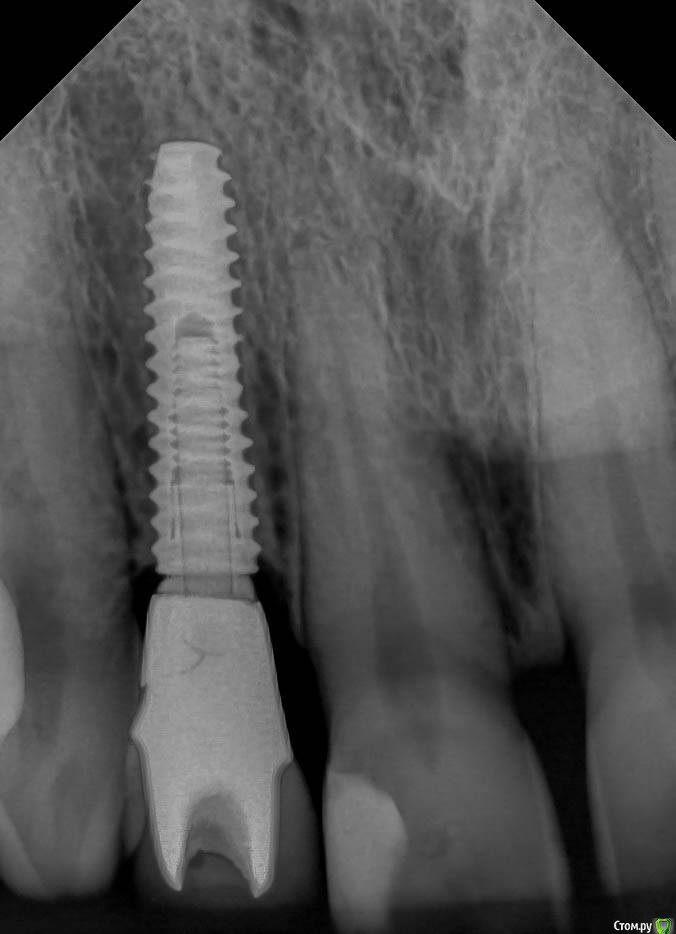

Smileee Опубликовано 15 ноября, 2018 Поделиться Опубликовано 15 ноября, 2018 (изменено) На втором снимке трещина абатмента? Изменено 15 ноября, 2018 пользователем Smileee Ссылка на комментарий

kamranchick Опубликовано 15 ноября, 2018 Автор Поделиться Опубликовано 15 ноября, 2018 На втором снимке трещина абатмента? как сказал ортопед, отклеился циркон от Ti-Base и он треснул Ссылка на комментарий

Smileee Опубликовано 15 ноября, 2018 Поделиться Опубликовано 15 ноября, 2018 как сказал ортопед, отклеился циркон от Ti-Base и он треснулКМК если б циркон отклеился, он бы вместе с коронкой выпал бы. Скорее всего просто абатмент треснул, без отклейки. 2 Ссылка на комментарий